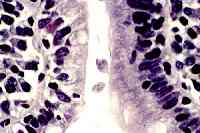

Formato Gráfico FIF

Los sístemas de compresión de imágenes con tecnología fractal (FIF: fractal image format) obtienen tamaños y calidad similares a los métodos más extendidos de tipo JPEG, con la ventaja de poder realizar funciones de zoom sobre las imágenes con muy escasa perdida de definición.

Las imagenes FIF permiten variar el numero de colores, cambiar a escala de grises, ver a pantalla completa, realizar rotaciones e inversiones y ampliar puntos o áreas de la imagen. Todo ello sobre la propia imagen que presenta el navegador, sin necesidad de grabarla en nuestro disco duro y aplicarle un software de tratamiento de imágenes. Los siguientes ejemplos permiten ver las carácteristicas de este formato gráfico.